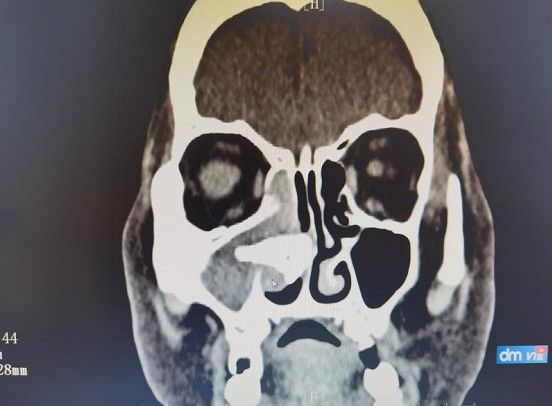

经过CT进一步确认,余婆婆右侧鼻腔内软组织密度影伴钙化。结合病理结果,确诊为鼻石合并真菌感染。

孙苏光医生表示:“通过CT可以看出,余婆婆的鼻石比较大,已经破坏了鼻中隔、鼻腔外侧壁骨质,并侵蚀了部分鼻泪管骨质,而且距离眼眶也非常近,如果再不手术取出,鼻石、真菌侵入眼内,将会造成眼眶感染,甚者会导致颅内感染。”